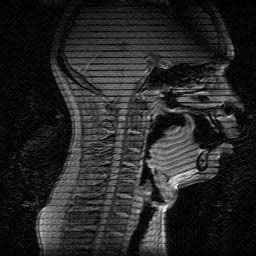

Vocal tract images are made in multiple planes during sustained speech sounds. Tagged Cine-MRI (tMRI) allows tracking of tissue points in oral structures.

![]() |

Subject saying /r/ |